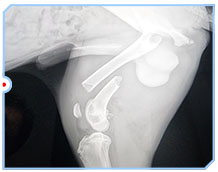

We need help to save Hank. Hank was found out in the middle of nowhere with what looked like a broken leg. His new dad works for the Sheriff's Dept and was sent out to check on him. He took Hank home, then to the vet, and his femur is broken. He is between 6-8 months old, so surgery with plates/screws is the best option for complete recovery. Hank has found his forever home, and is getting along great with his new canine siblings. Surgery will cost about $4000.